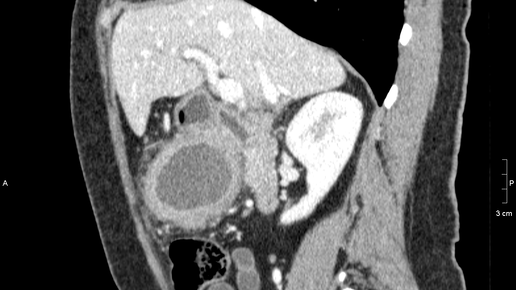

Магнитно-резонансную томографию активно используют для оценки состояния органов, расположенных в брюшной полости и забрюшинном пространстве. Полученные снимки позволяют выявлять нарушения в пищеварительном тракте и мочеполовой системе, а также в лимфатических сосудах. Исследованию подлежат поджелудочные протоки и желчные пути. При выявлении любых отклонений появляется возможность оценки тяжести имеющихся повреждений не только самого органа, но и прилегающих к нему тканей. Для исследования каких...

Магнитно-резонансная томография (МРТ) органов брюшной полости и забрюшинного пространства, включая почки и надпочечники, - это современный диагностический метод, не вызывающий дискомфорта и обеспечивающий высокую степень точности в обнаружении скрытых патологий. Суть метода заключается в получении детализированных послойных изображений внутренних органов и окружающих тканей, позволяющее обнаруживать даже мельчайшие изменения. Результаты проведённого исследования интерпретируются в заключении, выдаваемом специалистом-рентгенологом...